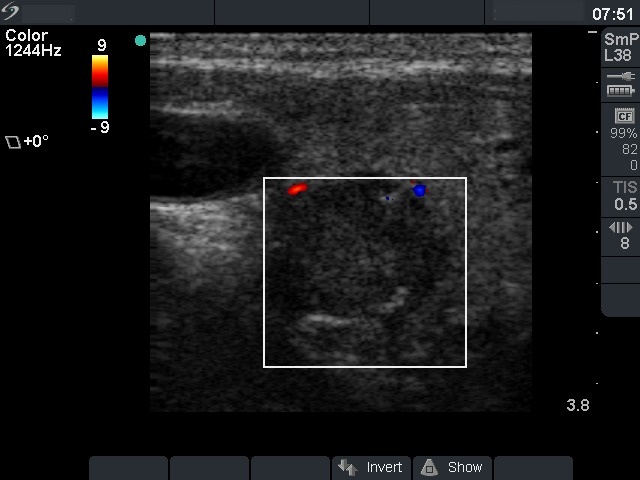

Ultrasonography. The right lobe was intact, while there was a hypoechogenic nodule in the left lobe. The lesion had hyperechogenic areas and coarse calcifications. A lymph node was detected lateral to the left thyroid.